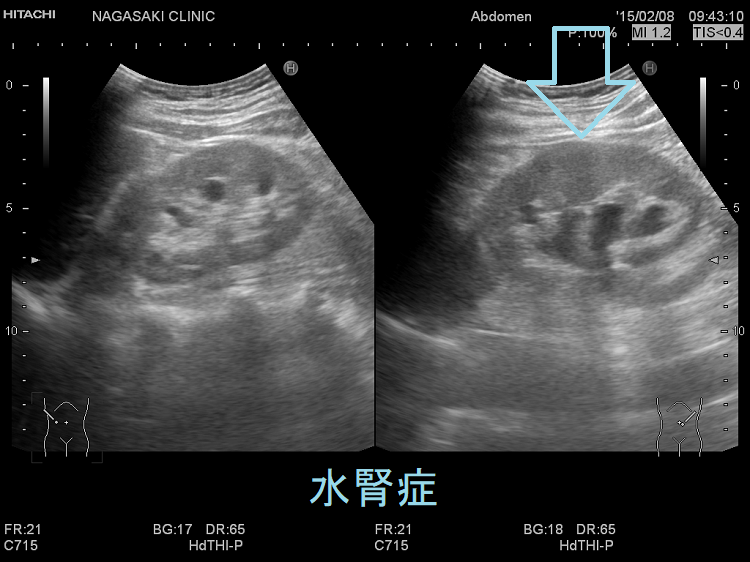

後腹膜線維症では、内臓を包む腹膜の背中側がガチガチに線維化します。腎臓から出て膀胱へ至る尿管を巻き込むため、尿の通過障害が起こります。結果、尿が腎臓へ逆流して、水腎症や急性腎盂腎炎を発症します。[Nephrol Dial Transplant. 2021 Sep 27;36(10):1773-1781.]

CT・MRIでは大動脈周囲に軟部影を認め、炎症性動脈瘤のような所見です。